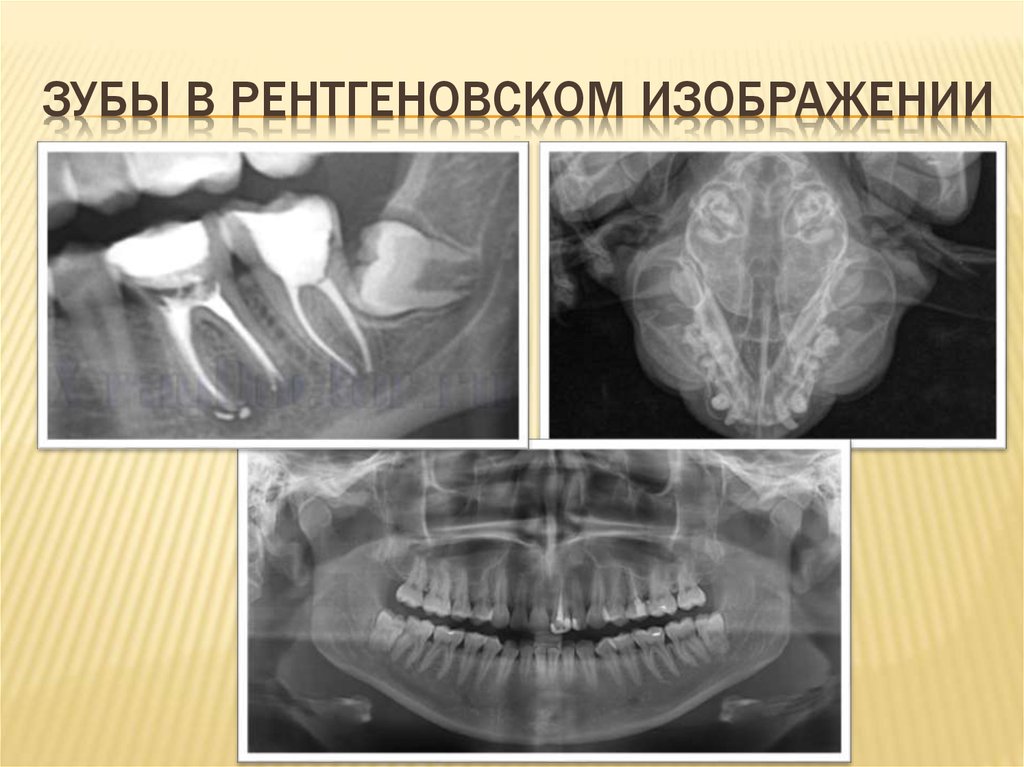

ЗУБЫ В РЕНТГЕНОВСКОМ ИЗОБРАЖЕНИИ